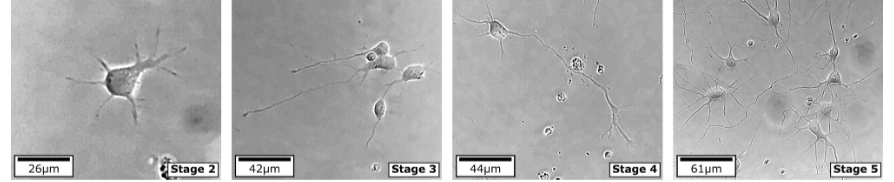

ML Future Frame Prediction (Video) using MetaFormer Attention for Biological Cultures

Future video prediction architecture for biological neurite outgrowth and deterioration.

K. Qian, G. O. Suarez, T. Nambara, T. Kanekiyo, Y. J. Zhang. High-throughput machine learning framework for predicting neurite deterioration using MetaFormer attention.Computer Methods in Applied Mechanics and Engineering 442, 118003, 2025.

Computational Modeling of Alzheimer's disease with Real Patients’ Neuron Cell

K. Qian, G. O. Suarez, T. Nambara, T. Kanekiyo, A. S. Liao, V. A. Webster-Wood, Y. J. Zhang. Neurodevelopmental Disorders Modeling using Isogeometric Analysis, Dynamic Domain Expansion and Local Refinement. Computer Methods in Applied Mechanics and Engineering, 433: 117534, 2025.